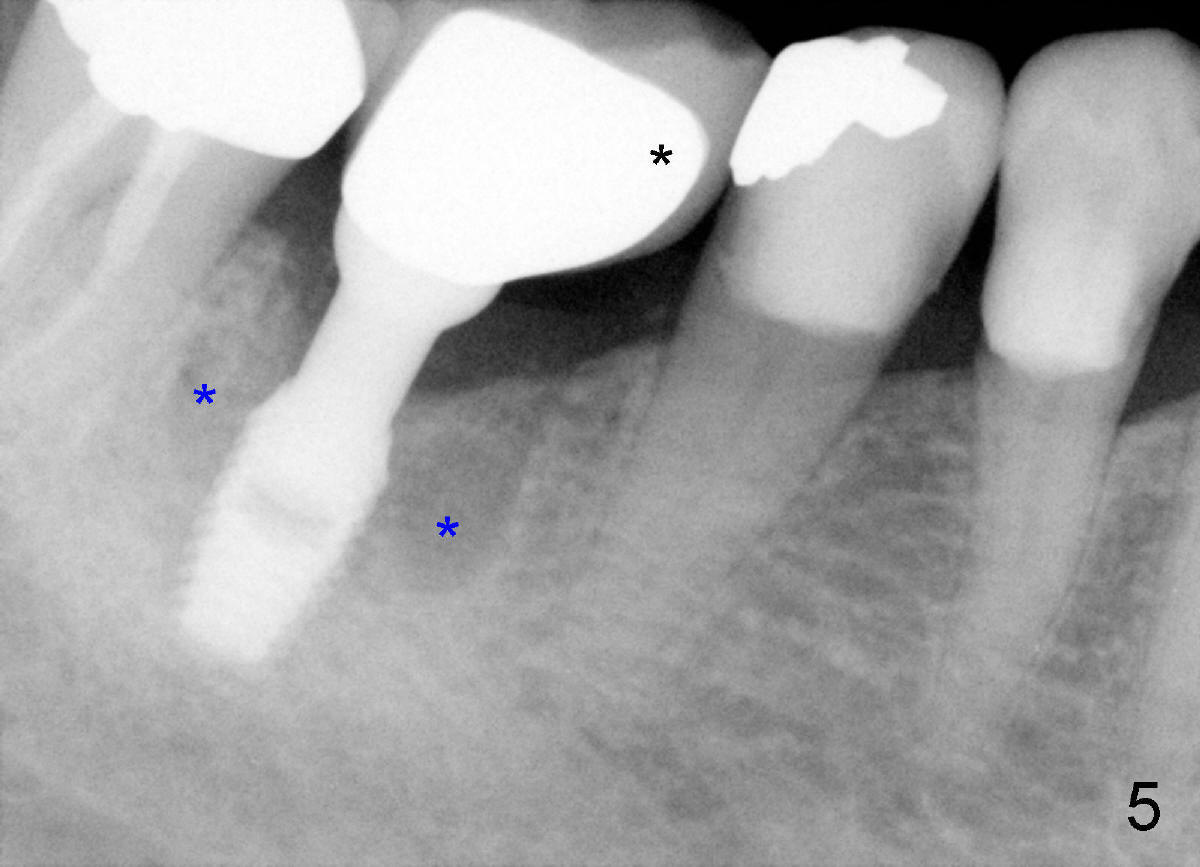

Heavy mastication tends to break not only natural dentition, but also restoration. The crown should be made of full metal, or Zirconium. Or PFM crown should be supported by larger metal framework (Fig.5 black *). This implant is placed off center (in the distal socket). Fig.5 X-ray is taken on the day of PFM cementation. Three years and a half later, there is no porcelain chip (Fig.6), while the bone density around the implant is increased (blue *), as compared to those in Fig.5. In fact the larger metal framework is designed and fabricated by a large dental lab in Florida (Smith-Sterling).